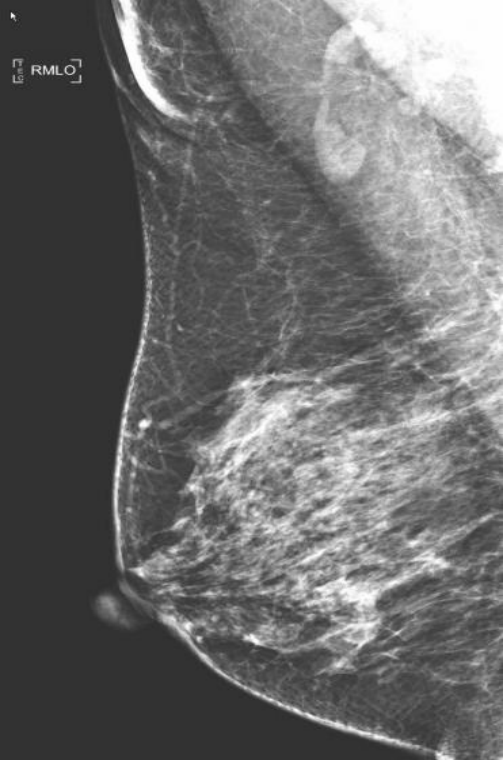

(3)非高危女性从40周岁开始,每年做一次乳腺钼靶筛查;对于有乳腺癌家族史者、未育、月经初潮早等高危因素的女性从35周岁开始,每年做一次乳腺钼靶筛查。而且,女性最好选择在经期结束3-7天进行乳腺钼靶检查。数字化乳腺钼靶是目前国际推荐的乳腺癌筛查手段。

(3)配备高效能非晶硒平板探测器,覆盖视野大,空间分辨率高,像素尺寸小,自能分析调节图像灰阶度、对比度,使图像清晰度达到最大化,可完整显示整个乳腺及腋窝淋巴结区域。

乳腺X线检查是提高乳腺癌早期诊断的主要手段。全数字化平板乳腺机在早期临床诊断乳腺疾病中具有举足轻重的地位。